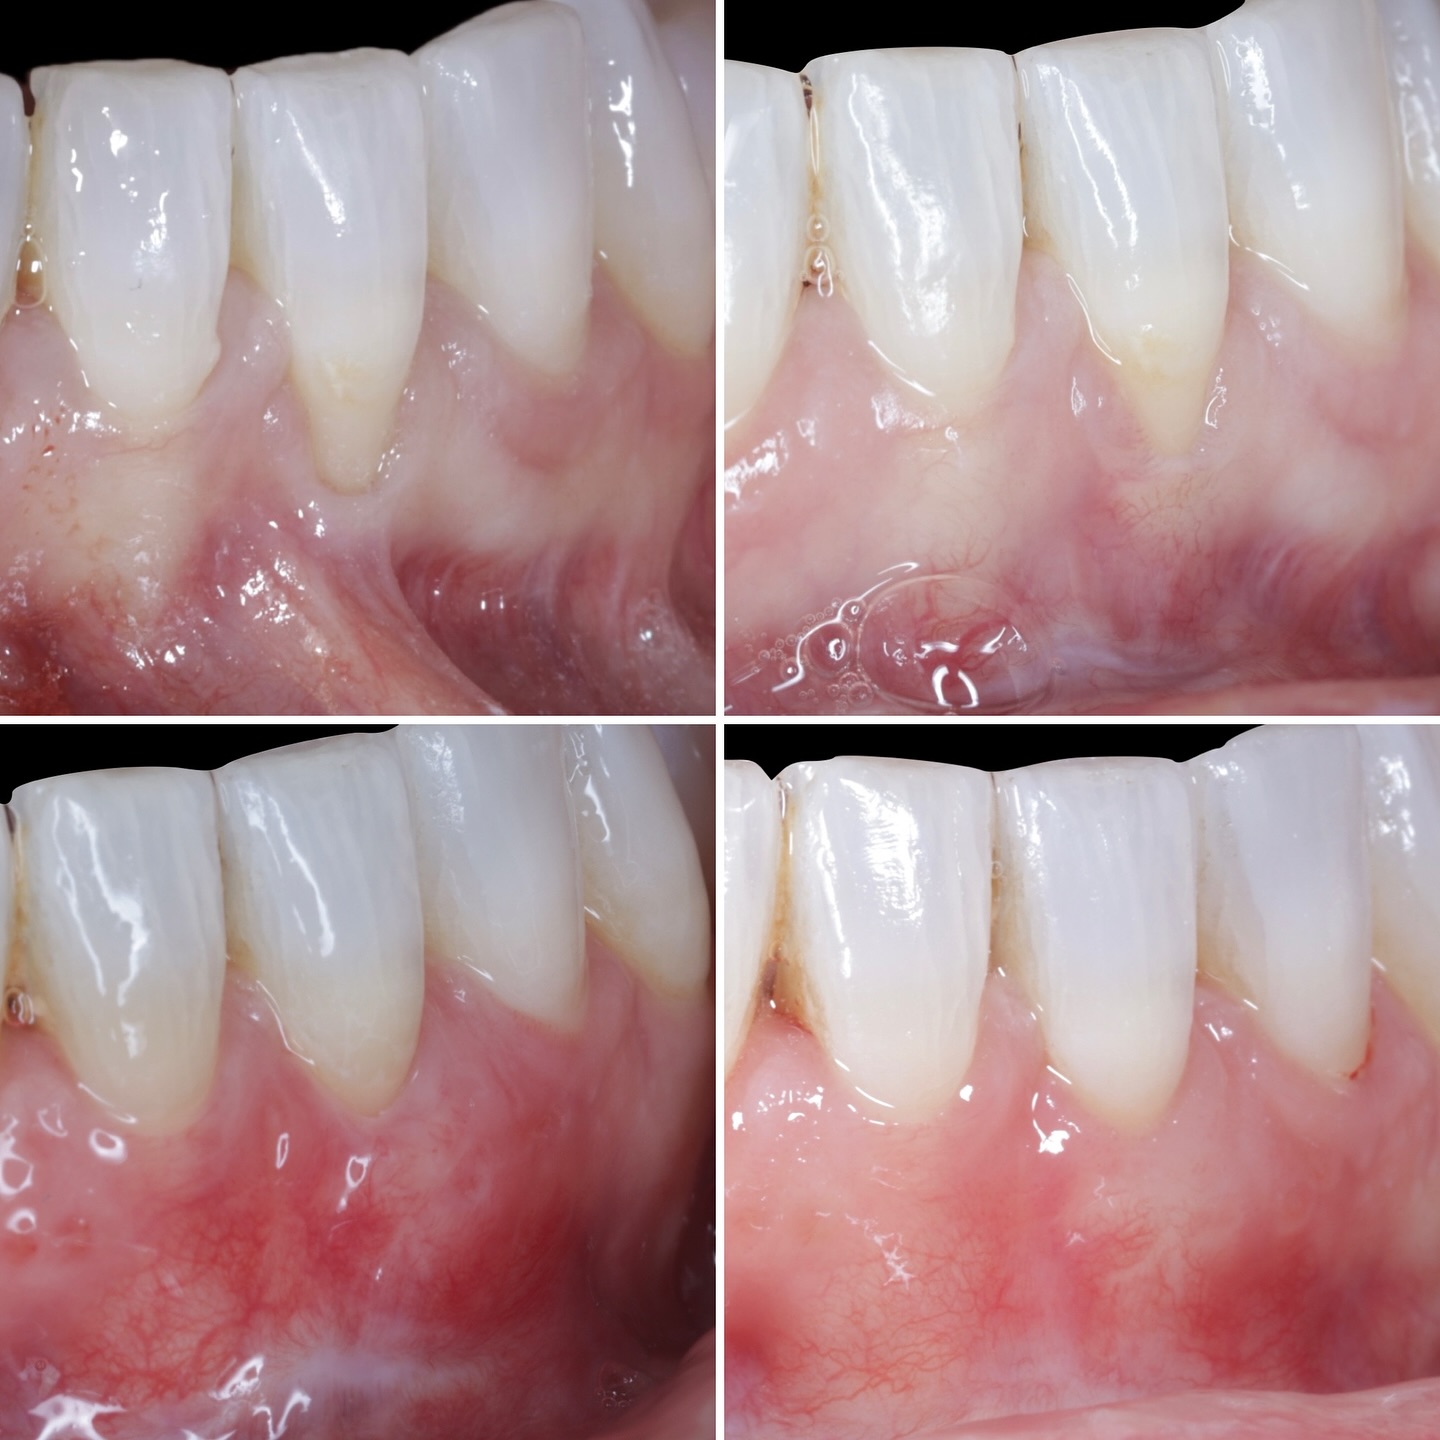

Durante una mañana, asistirás a una Cirugía Mucogingival de recubrimiento radicular de recesiones múltiples en IV y V sextante (36 a 43).

Gracias al uso del microscopio y a la proyección en tiempo real en pantalla, verás exactamente lo mismo que veo yo durante la cirugía, sin tener que estar

Podrás asistir a la planificación de casos y cirugía de injerto de tejido conectivo. Factores determinantes y elección de la técnica adecuada. Sumérgete en un protocolo predecible y técnicamente correcto para obtener resultados óptimos.

Aprende la planificación y técnica de la cirugía Mucogingival para el recubrimiento de recesiones y aumento de banda queratinizada en el sector anteroinferior

Una estancia clínica pensada para quienes quieran iniciarse o dar un paso más en el campo de la cirugía mucogingival. Durante esta experiencia tendrás la oportunidad de aprender en directo cómo se planifica y se lleva a cabo una cirugía mucogingival mediante técnica de Túnel.

La sesión